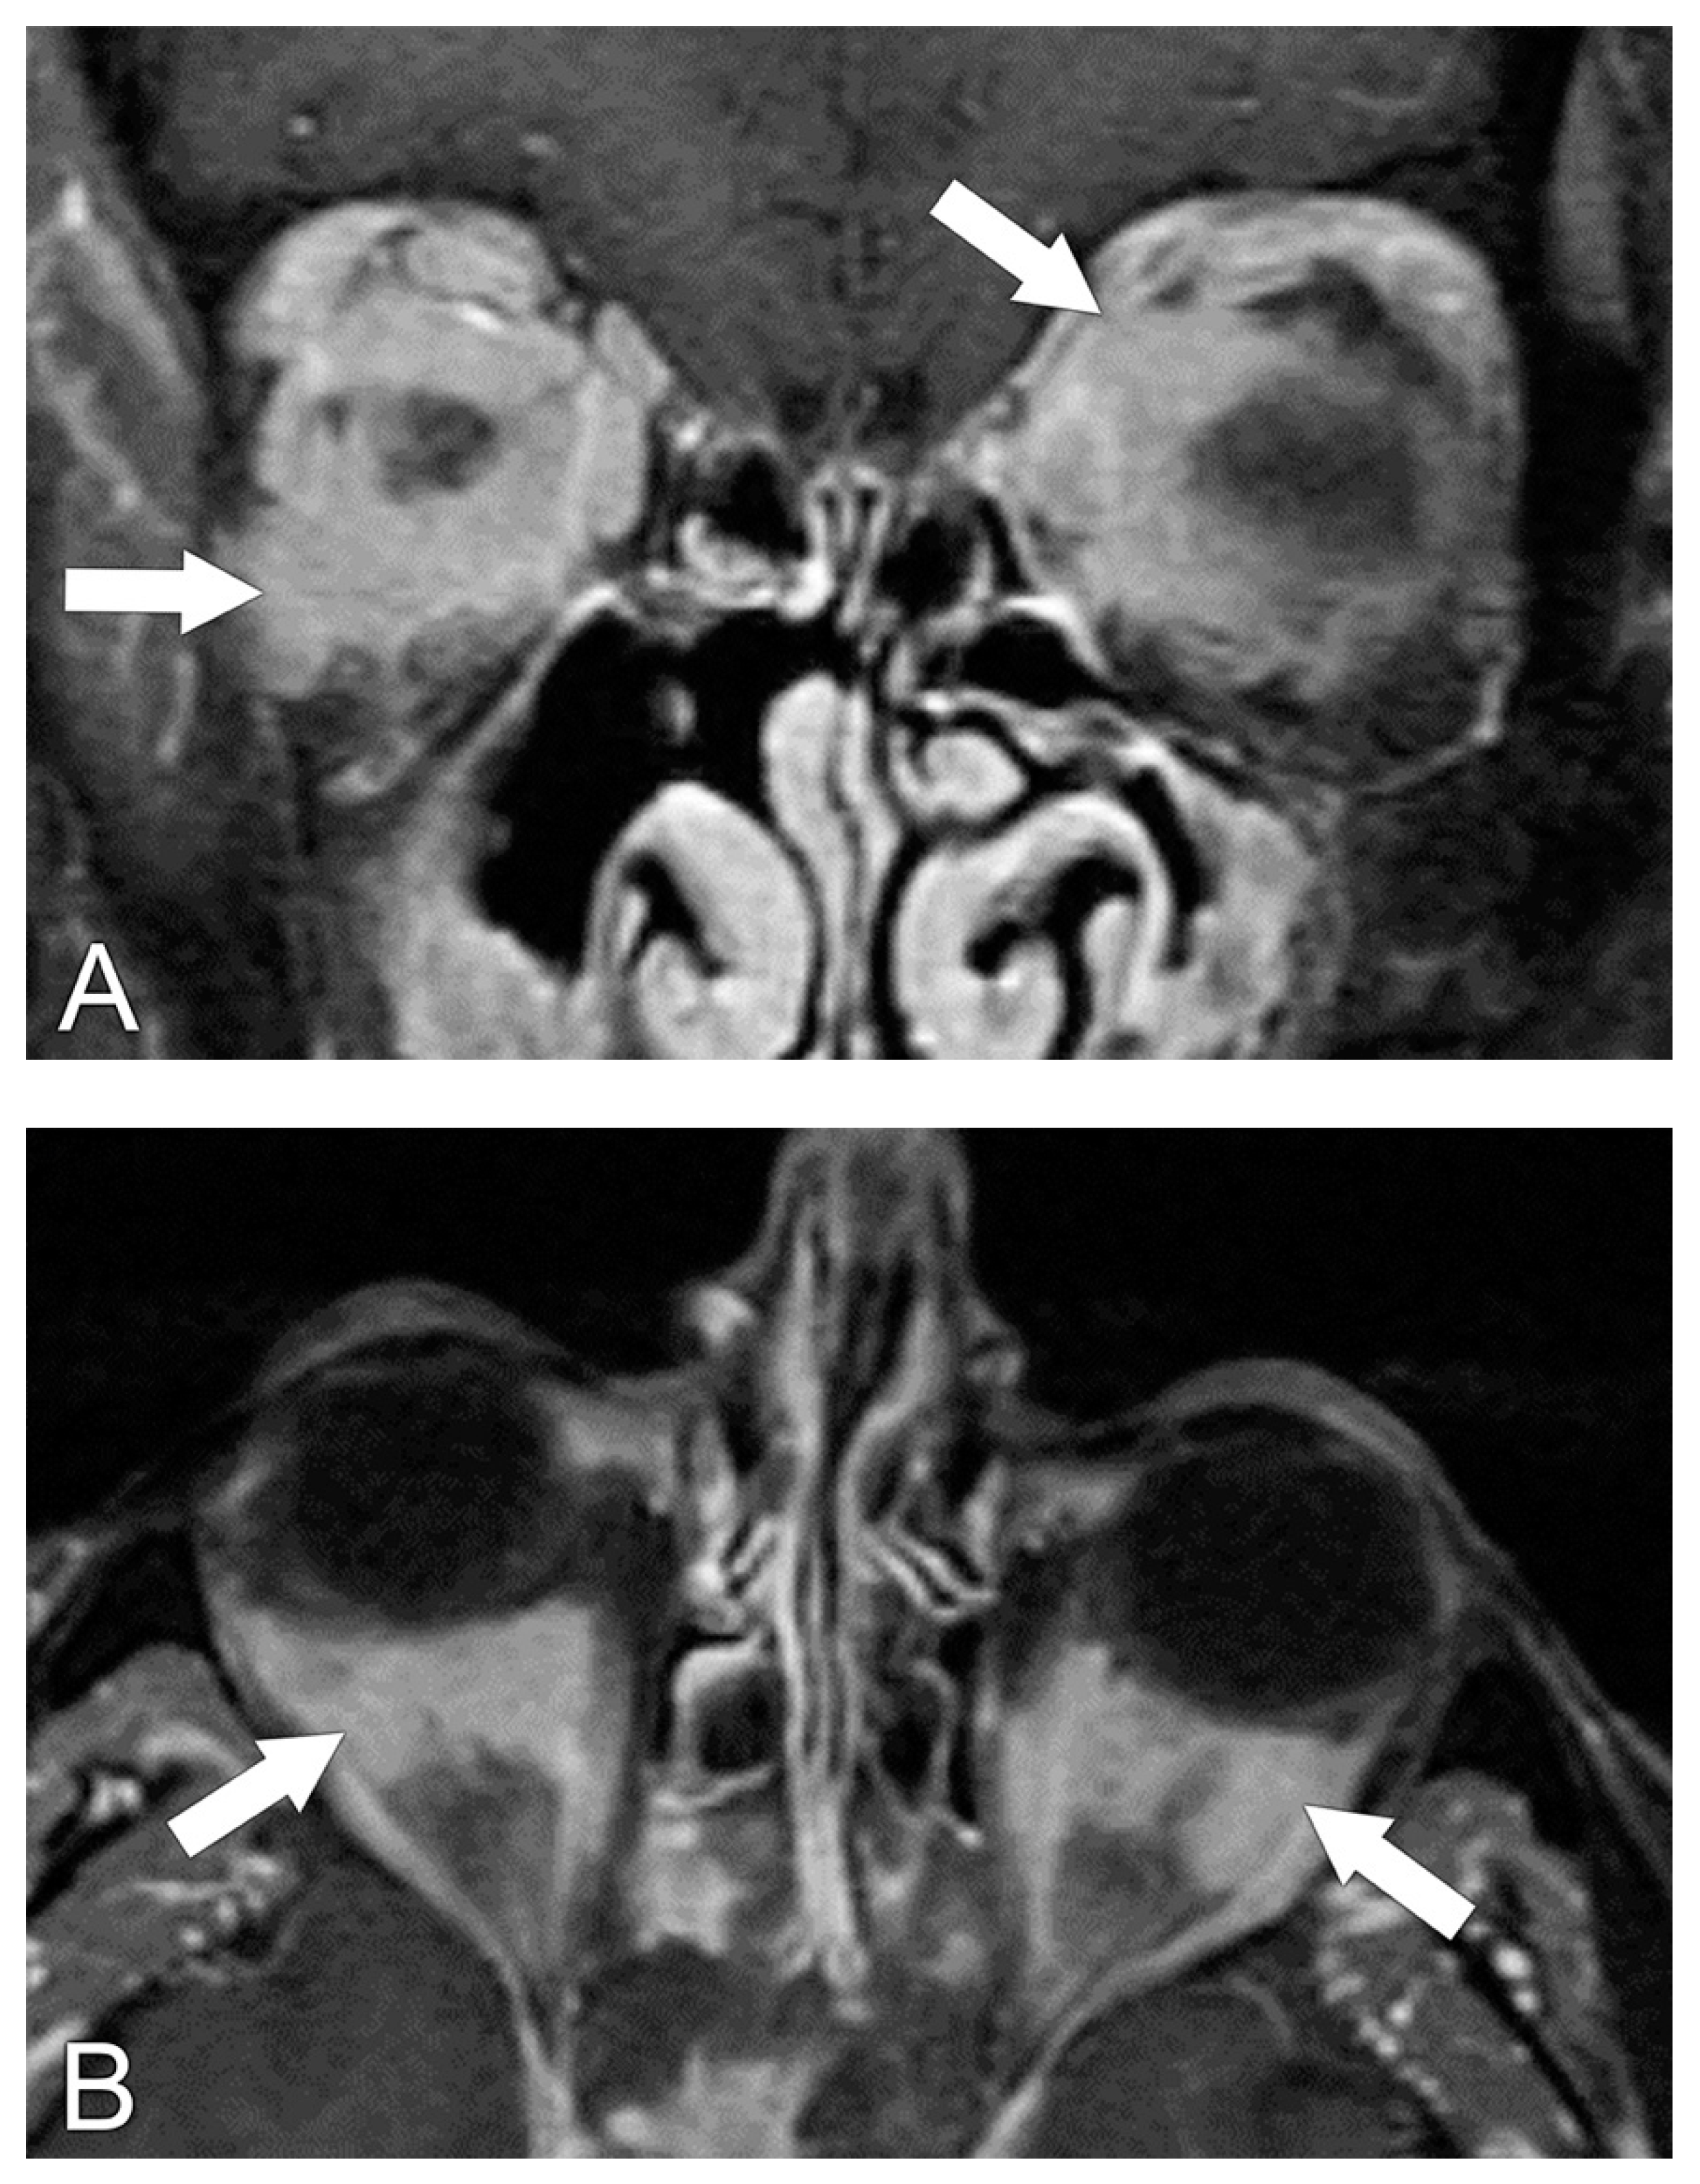

5.2. Magnetic Resonance Imaging (MRI)

6. Radiological Differential Diagnosis